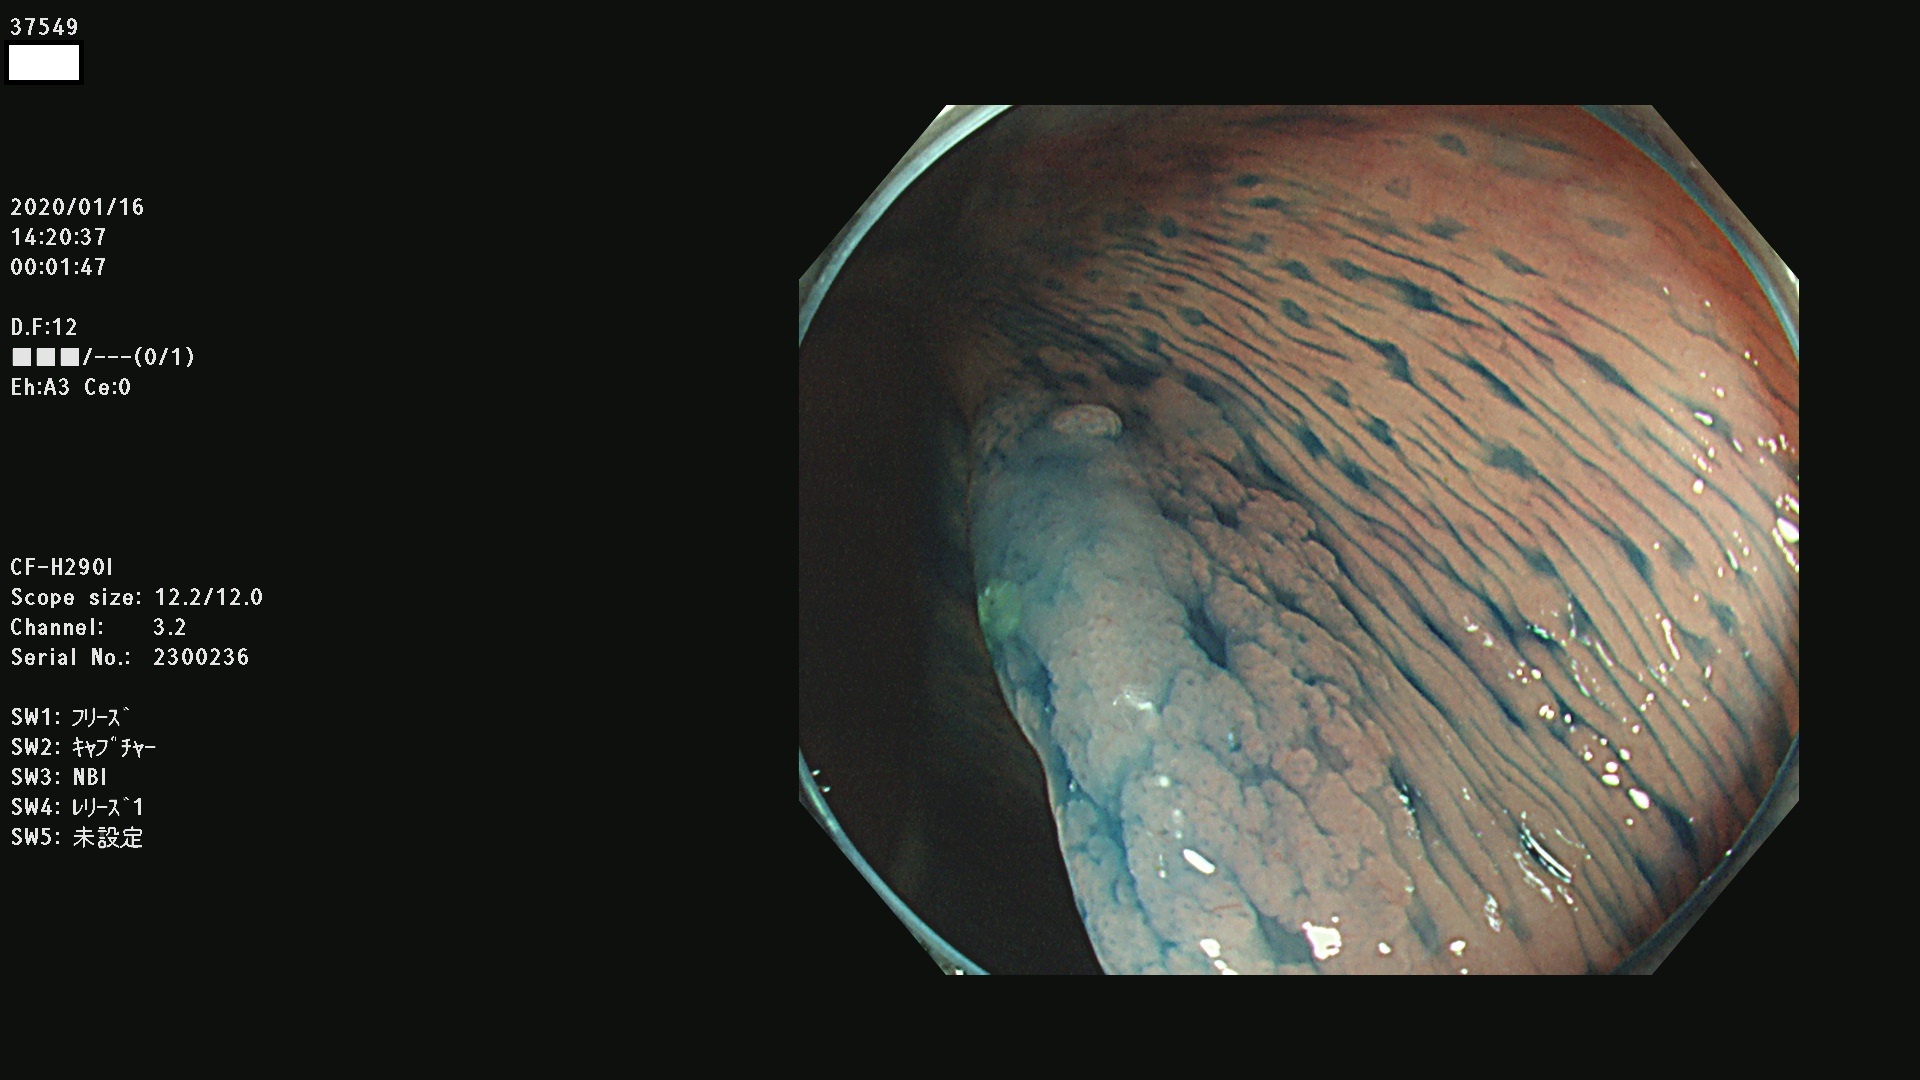

腺腫発見率 67 % (カルテ番号 37500〜37599の100名の方の検査結果で集計)大腸癌検診最新情報

以下のカルテ番号の方に腺腫(Adenoma,Group3〜5)が見つかりました(集計法)

37500 37502 37503 37505 37508 37509 37510 37511 37512 37513 37514 37517 37519 37520 37521 37525 37526(SSAPのみ) 37527 37528 37529 37531 37532 37533 37534 37536 37538(SSAPのみ) 37539 37541 37542 37543 37547 37548 37549(SSAPのみ) 37550 37552 37555 37556 37561 37562 37563(SSAPのみ) 37564 37565 37566 37567 37568 37570 37571 37572 37573 37574 37575(SSAPのみ) 37576 37577 37579 37580 37582 37583 37586(SSAPのみ) 37587 37588(SSAPのみ) 37590 37593(SSAPのみ) 37594 37596 37597(SSAPのみ) 37598 37599

発見困難で危険性の高い平坦型病変(上記100名より抽出) ![]()